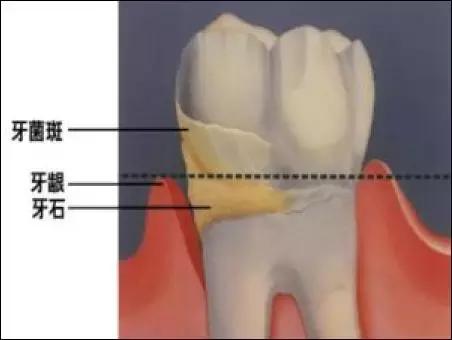

牙石位于牙颈部表面,牙龈缘以上尉龈上牙石,牙龈缘以下为龈下牙石。龈上牙石常呈黄色或灰白色,也可因吸烟或被食物色素着色而变为深色。牙石容易沉积在唾液腺导管开口相对的牙面上,如下前牙舌面(内侧)和上后牙颊(外侧)。此外,牙石还沉积在失去咀嚼功能的牙面上,如错位牙及单侧咀嚼习惯者的无功能侧牙齿颌面。